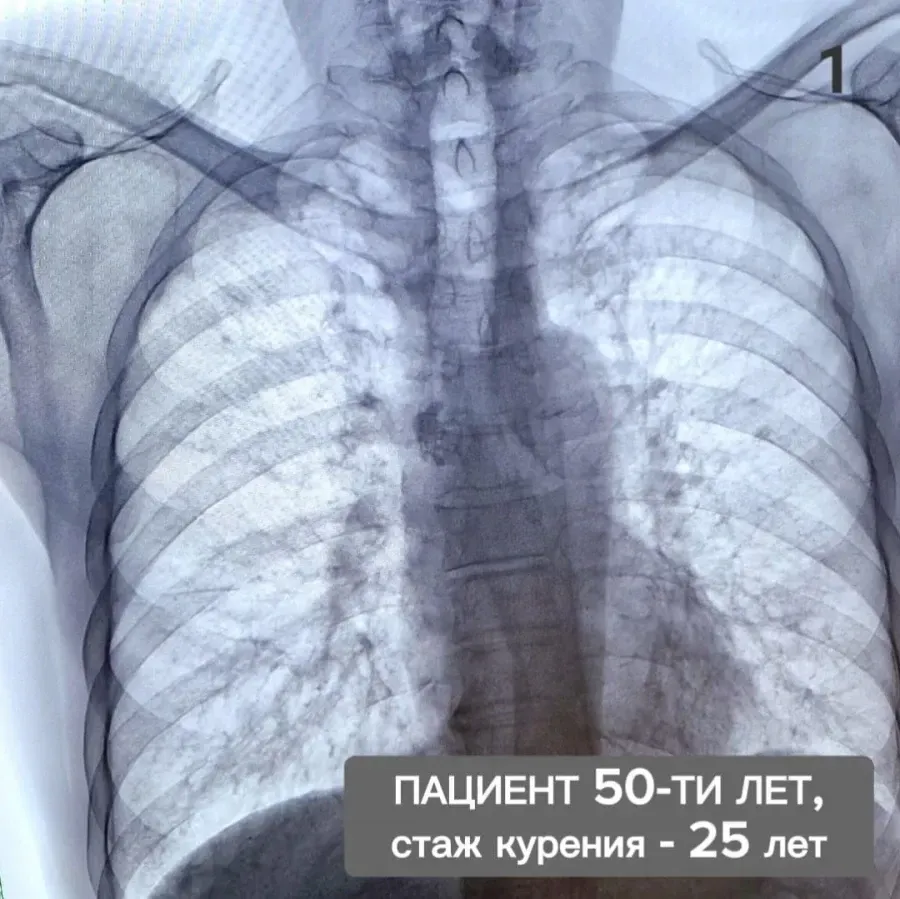

Изучение дозы излучения при рентгеновских исследованиях: визуализация